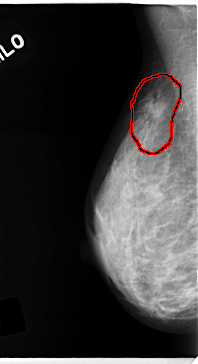

RIGHT_MLO LINES 4720 PIXELS_PER_LINE 2568 BITS_PER_PIXEL 12 RESOLUTION 50 OVERLAY

FILE: C_0139_1.RIGHT_MLO.OVERLAY

TOTAL_ABNORMALITIES 1

ABNORMALITY 1

LESION_TYPE MASS SHAPE IRREGULAR MARGINS SPICULATED

ASSESSMENT 5

SUBTLETY 4

PATHOLOGY MALIGNANT

TOTAL_OUTLINES 1

BOUNDARY